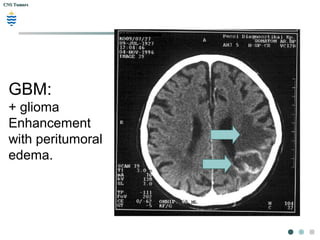

GBM:

+ glioma

Enhancement

with peritumoral

edema.